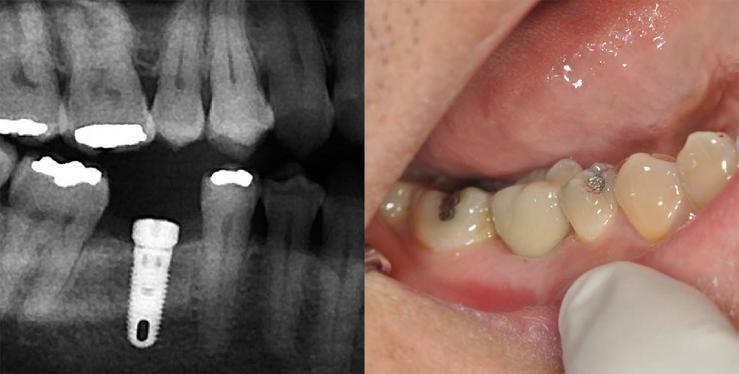

On the x-ray, looking at the lower left first molar, tooth #30, the white lines in the center of the roots is a root canal filling.   In this case, the root canal has failed. Below the roots, there is a dark area which represents a chronic abscess full of bacteria.   To the right is white oval.  That is a ball bearing that is used to calibrate the x-ray so that we can digitally measure  height.

The implant is placed. The post operative pain is usually gone in a day. We wait 4 to 6 months for the bone to heal and mature.  The image on the left is an x-ray of the implant and a healing collar or a small temporary cap that is screwed on top of the implant. Once fully healed, then a titanium abutment is screwed in and a porcelain crown is cemented on the abutment (right image).   Implant placement and restoration by Dr. Gerald Au